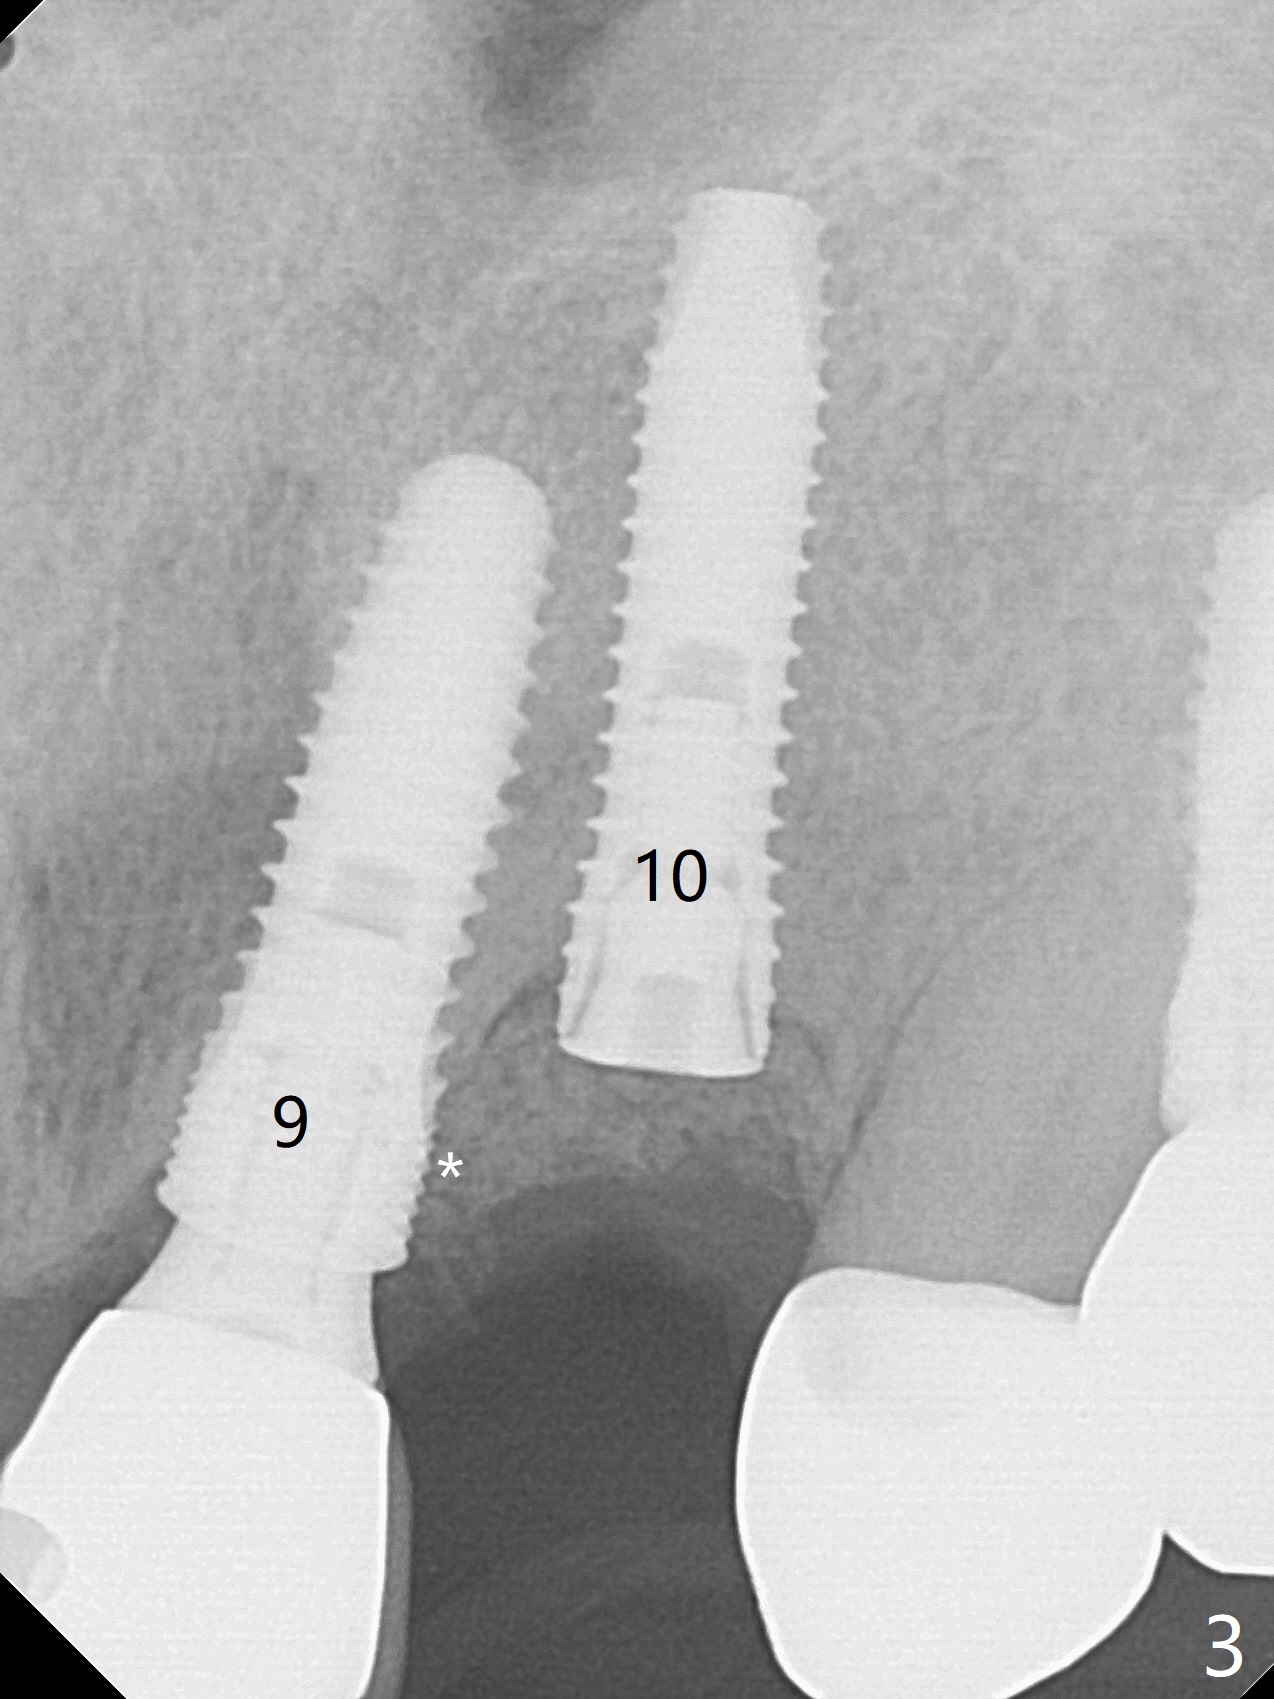

10号牙第三次种植后四年,病人主诉疼痛,颊侧牙龈缘轻度红肿,牙冠与基台取出(没有使用扳手,说明基台未完全就位),切开时,10号牙植体暴露却不多(图一),而9号牙植体远中微型螺纹却暴露很多(图二:*),整个植体种的不够深(图三),如果粘性骨块(*)不能解决周围炎问题,考虑拔除9号牙植体,做悬臂桥。Periodontal dressing dislodges 6 days postop (Fig.4).